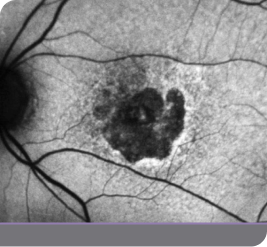

Case study of a GATHER2 clinical trial patient

This is the experience of a 79-year-old female with bilateral GA who reported good vision but said she needed a magnifying glass to read the newspaper

The patient was enrolled in the IZERVAY clinical trial for treatment of the right eye, and the left eye was observed. 2.5 years after initiating treatment in the right eye, product became available and the left eye was treated with IZERVAY.

• Baseline vision was 20/40 OD and 20/63 OS

• In the right eye, there was a 4.01-mm2 nonsubfoveal GA patch

• In the left eye, there was a 0.77-mm2 patch of GA inferiorly

• Hyperfluorescence at the lesion border signifies disease activity and is an indicator of progression

In this patient, IZERVAY slowed lesion growth over time

IZERVAY-treated right eye (OD)

Untreated left eye (OS)

1y 1m

2y 11m

Left eye (OS) treated with IZERVAY at 2.5 years

OD=oculus dexter; OS=oculus sinister.

Images courtesy of Dr. Beth Richter.

This is an individual patient case study. It should be interpreted with caution and cannot be considered conclusive. Individual results may vary. In the GATHER trials, sham was used as the comparator.